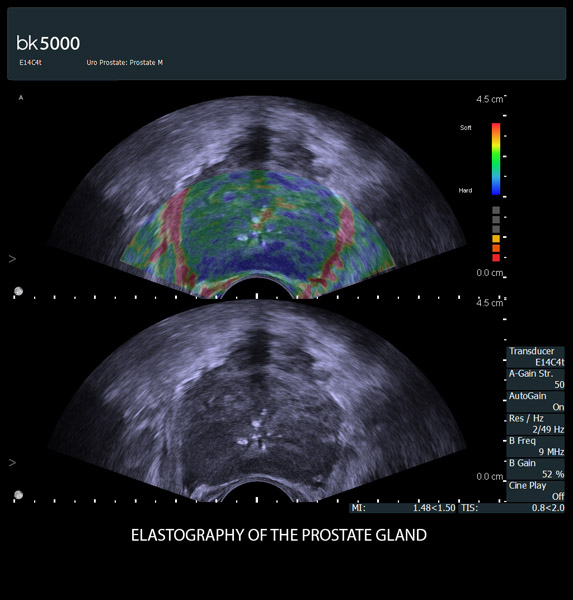

You know what you need, and you need it fast. That’s why the bk5000 is designed to deliver the high resolution images you count on quickly and efficiently. Whether you’re identifying margins of a lesion or making a general assessment of an area of interest, the bk5000 has the power and performance to meet your needs on your terms.

From the simplest diagnostic imaging to the most critical interventional procedures, every clinical situation has its own set of unique challenges. The bk5000 offers a full suite of innovative technologies and advanced controls and adjustments to help you achieve the best possible image quality, across many applications.